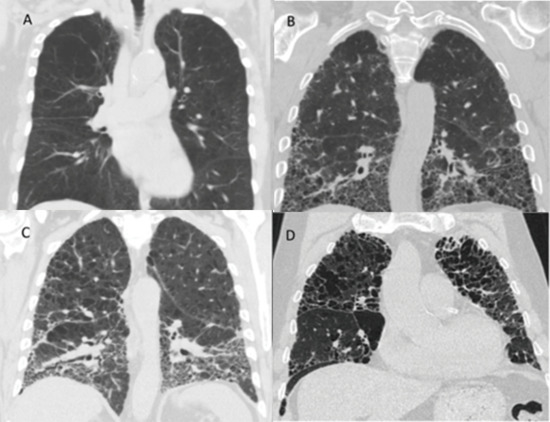

4. Combined Emphysema and Fibrosis